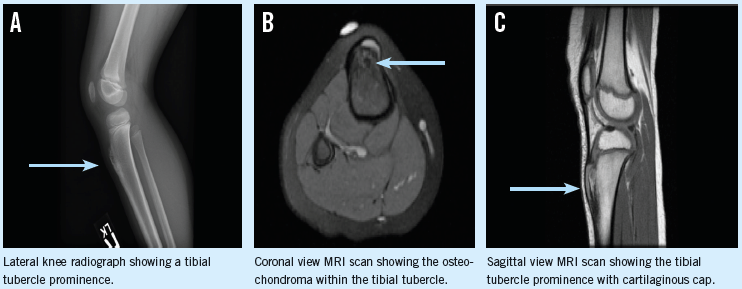

Elizabeth Badowski, MS, CNP

A 6-year-old girl presented to a pediatric orthopedic surgeon for evaluation of a prominence below her right knee.